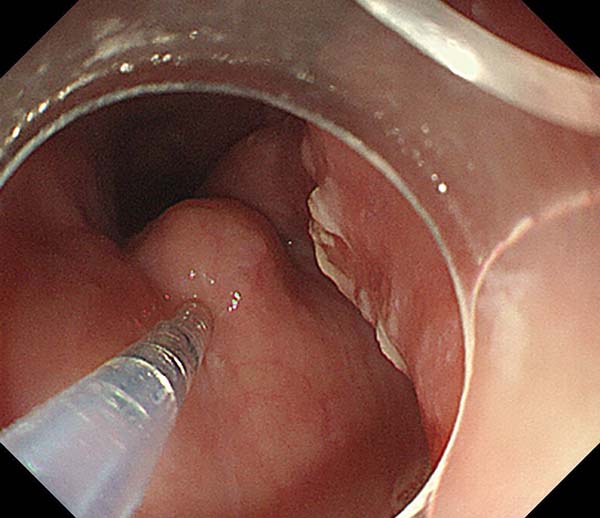

8 个月前,老吕因进食后出现哽噎感,前往北京一家三级医院的消化内科就诊。经过检查一喜一忧两个消息让老吕犯了难。好消息是,内镜下并未呈现出食管癌的典型表现;但坏消息却是,食管上确确实实长了个东西,其表面黏膜光滑,很可能源自黏膜下层。超声内镜和胸部 CT 给出的诊断结果显示肿物肿物大小足有 5 公分,来源于食管固有肌层,平滑肌瘤的可能性较大,但它向内压迫食管管腔,致使食管狭窄,进而造成了进食后的哽噎感症状,向外突出于食管外壁,并且与支气管、主动脉关系紧密。

消化内科主任何玉琦给出建议,肿物的壁内部分可以采用STER手术,也就是内镜经黏膜下隧道肿物切除的方式进行。简单来说,就是在食管壁上打一个隧道,进入病灶部位,将病灶与正常的食管壁分离,随后关闭隧道,这样能够最大程度上保持食管壁的完整性,避免穿孔和食管瘘的形成。随后再由外科医生进行壁外部分的分离。手术结束后,再进行一次胃镜检查,明确有无瘘和狭窄等情况,同时胃镜下置入一根空肠营养管,恢复期间采用营养管肠内营养,为食管黏膜愈合提供条件,最大程度上避免食管瘘的形成。就这样,医院最终决定,采用胸腔镜、消化内镜“双镜合璧”的方式为患者进行食管平滑肌瘤切除术。

方案确定,第二天,老吕的手术如期进行。在手术室和麻醉团队的保驾护航下,消化内科操纵着消化内镜完成肿物与黏膜层的分离,随后胸外科用单孔胸腔镜游离肿瘤与食管肌层,完整切除并取出肿物,缝合食管肌层,最后消化内镜再次检查食管黏膜无破损,食管无狭窄,使用金属夹封闭隧道,并置入空肠营养管。3个小时,手术顺利完成。一个7.0*3.0*2.0cm的肿物被完成切除。